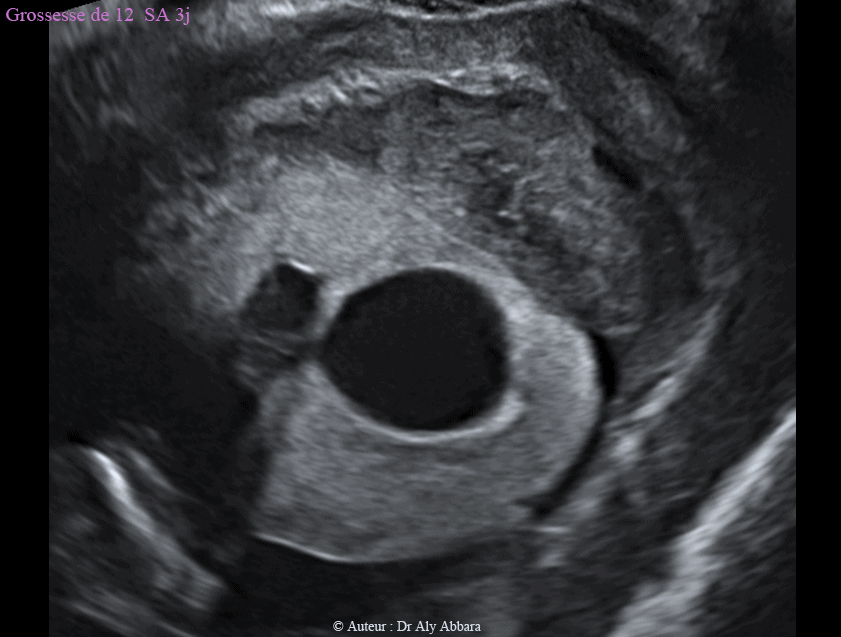

Kyste cytotrophoblastique itraparenchymateux (intraplacentaire) associé à la présence d'un hématome rétroplacentaire - grossesse de 12 SA et 3J

Hématome rétro-placentaire et rétro-cervical utérin en association avec la présence d'un kyste placentaire cytotrophoblastique intra-parenchymateux chez une femme enceinte de 12 SA et 3 J

• Dans le cas présenté dans cet article, les images échographiques montrent la présence d'un décollement partiel du placenta aboutissant à la formation d'un hématome rétro-placentaire " HRP " (et rétro-cervical utérin) de 42 x 21 x 52 mm de diamètre (soit 24 cm3 de volume).

Cet HRP se manifeste cliniquement par des métrorragies modérées depuis plusieurs semaines, mais la grossesse évolue normalement : foetus vivant et morphologiquement normal, avec longueur crânio-caudale "LCC" = 61,75 mm, et clarté nucale = 1,51 mm.

Cet hématome rétroplacentaire (HRP) est en association avec la présence d'un kyste placentaire de type cytotrophoblastique intra-parenchymateux prenant l'aspect d'une formation kystique intra-placentaire, unique, uniloculaire, à contenu anéchogène et à paroi hyper-échogène, mais sans végétations endophytiques et sans zone d'épaississement.

Ce kyste évolue dans le parenchyme placentaire, mais au niveau d'un de ses deux pôles, il atteint la face fœtale du placenta à un point correspondant à la zone de l'insertion du cordon ombilical.

Le kyste mesure 26 x 21 x 23 mm de diamètre (soit 6,4 cm3 de volume).